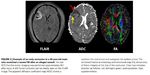

Neuro - Bildgebung

ADC: Apparent Diffusion Coefficient

(Diffusionskoeffizient)

diffusion of water molecules to generate

contrast in MR images

hohe ADC: vasogenes Ödem

niedere ADC: zytotoxisches Ödem, Ischämie

Frontiers Neurol. 2015